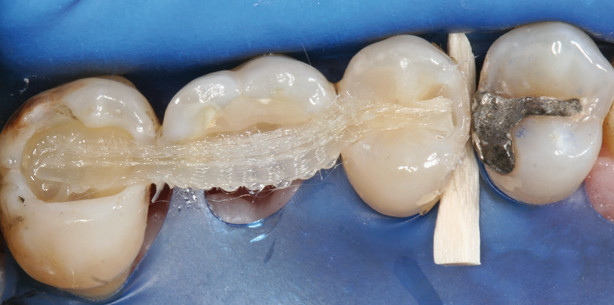

Das vierte Röntgenbild zeigt Zahn 26 nach Wurzelamputation der distalen und palatinalen Wurzel. Intraoperationem erwies sich die Grad-III-Furkation auch mesiopalatinal durchgängig und die palatinale Wurzel als nicht mehr erhaltungsfähig. Die fünfte Röntgenaufnahme zeigt Zahn 26 geschient mit F-Splint-Aid Slim an den Zähnen 25 und 27 (Abb. 4–5).

Die klinische Fotostrecke zeigt die Vorgehensweise des Zahnschienens mit dem F-Splint-Aid Slim System in der direkten Adhäsivtechnik (Abb. 6–19).